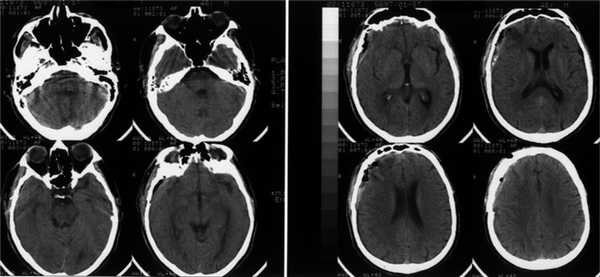

Анализ крови на алкоголь — 0 промилле. Выполнена диагностическая люмбальная пункция, выявлено субарахноидальное кровоизлияние: 10-15 эритроцитов в поле зрения. При помощи эхоэнцефалоскопии обнаружено смещение срединных структур головного мозга на 3-4 мм влево. Т.е. у пациента имеются клинические данные, указывающие на внутричерепную гематому справа, но при отсутствии КТ/МРТ-диагностики определить её объём и локализацию сложно. Для дальнейшего диагностического поиска пациенту выполнена церебральная ангиография. На ангиограммах отмечено отжатие сосудистой сети правого полушария головного мозга от костей свода черепа почти на 10 мм (рис. 1). В левом полушарии патологии не выявлено (рис. 2).

Острое нарушение мозгового кровообращения по геморрагическому типу с формированием острой субдуральной гематомы в правой лобно-височно-теменной области. Артерио-венозная мальформация в лобной области справа.

Данный клинический случай показывает, что при отсутствии КТ/МРТ ангиографическое исследование позволяет локализовать внутричерепную гематому и приблизительно оценить её объём. Источник гематомы верифицирован также благодаря этому виду обследования. Если почитать старые руководства по нейрохирургии 70-80-х годов прошлого века, можно убедиться, что церебральная ангиография очень часто применялась для диагностики гематом головного мозга, опухолей, не говоря уже о сосудистой патологии.